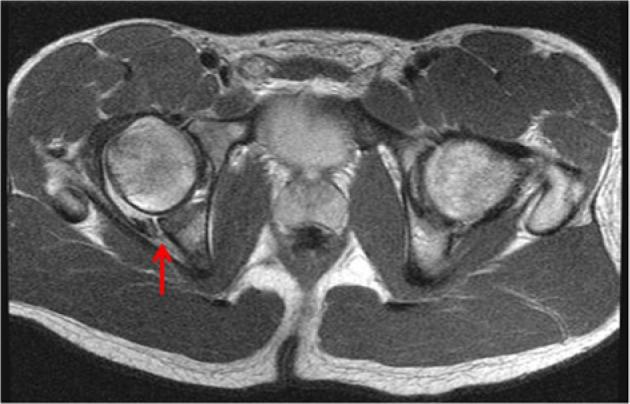

Increased stresses across the bony hemipelvis result when athletes with FAI attempt to achieve supraphysiologic, terminal ranges of motion (ROM) through the hip joint required for athletic competition. This can manifest as pain within the pubic joint (osteitis pubis), sacroiliac joint, and lumbosacral spine. Subclinical posterior hip instability may result when attempts to increase hip flexion and internal rotation are not compensated for by increased motion through the hemipelvis. Prominence of the anterior inferior iliac spine (AIIS) at the level of the acetabular rim can result in impingement of the anterior hip joint capsule or iliocapsularis muscle origin against the femoral head-neck junction, resulting in a distinct form of mechanical hip impingement (AIIS subspine impingement). Iliopsoas impingement (IPI) has also been described as an etiology for anterior hip pain. IPI results in a typical 3-o'clock labral tear as well as an inflamed capsule in close proximity to the overlying iliopsoas tendon. Injury in athletic pubalgia occurs during high-energy twisting activities in which abnormal hip ROM and resultant pelvic motion lead to shearing across the pubic symphysis.